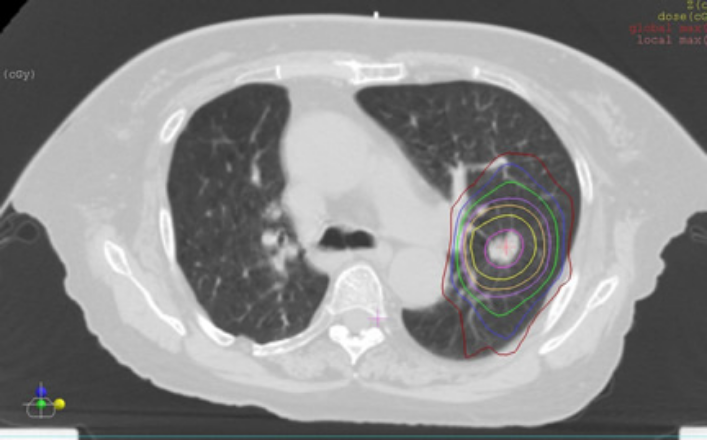

定位放射線治療はピンポイント治療と言われています。図1は定位放射線治療の線量分布図という設計図面で、放射線はがんに集中してあたっているのがわかります。がんのみに集中してピンポイントに大線量の放射線治療を行うことで治療効果が高く副作用の少ない治療を行うことができます。定位放射線治療を行った部分は、原発性肺がんで8割程度の確率で制御できます。標準的治療は外科手術ですが、何らかの理由で行えない患者さんにとってはよい治療方法と考えています。医師からのお話後、準備で2~3週間、治療は1日1回、1時間程度で、4~10日間で終了致します。照射中に痛みなど感じることはなく、両手を上げて動かずに仰向けに寝ていただているのみで治療可能です。この治療は、原発性肺がんのみでなく、転移性肺がんの治療も可能です。

図1